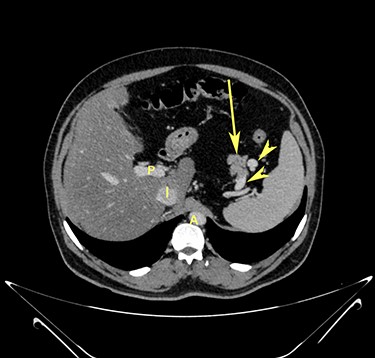

Transverse section image of a contrast-enhanced CT scan of the abdomen at level 2–2 (Fig. 1), showing the pancreas’ normal head and body (long arrow). The confluence of the splenic vein and portal vein are labelled using arrowheads.